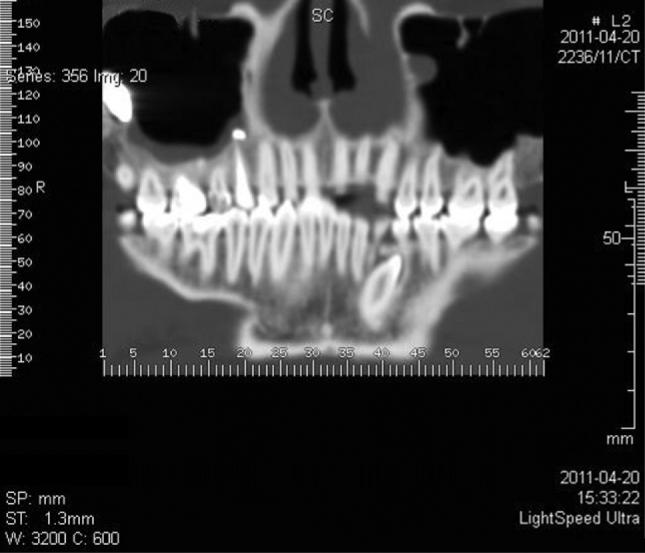

Foreign bodies found in the maxillary sinus include tooth roots, burs, dental impression material, root-filling materials, dental implants, and needles. The purpose of this paper was to present an unusual case of a large foreign body of endodontic origin (root-filling material) removed from the maxillary sinus. A 45-year-old generally healthy male patient reported to the Department of Conservative Dentistry with Endodontics of the Medical University of Silesia, because of orbital and buccal pain on the right side of his face and headaches in the preceding 6 months. Those symptoms were associated with the end of endodontic treatment of teeth 14 and 16. Periapical X-rays, including of teeth 14 and 16, showed the presence of root canal filling with extrusion of endodontic obturation material beyond the apices of tooth 14. In the case of tooth 16, a completely filled palatal canal and incompletely filled buccal canals were found. There was also an irregular dimness at the upper edge of the X-ray image. Panoramic radiography and computed tomography demonstrated a foreign body in the right sinus. Sinus exploration was performed via a surgical procedure conducted using topical anesthesia. The root apices of tooth 14 were resected, and foreign substance was removed. The practitioner did not correctly recognize a complication that occurred during endodontic treatment, which resulted in extrusion of endodontic material beyond the root apices of tooth 14. This case emphasizes the potential impact that an involved maxillary sinus may have on endodontic therapy. Detailed diagnostic identification based on the medical interview, physical and histopathological examinations, and diagnostic imaging allowed rapid surgical intervention and prevented local and general complications. It is important to realize that the range of the periapical X-ray projection is not always sufficient.

在上颌窦中发现的异物包括牙根、牙钻、牙科印模材料、根管充填材料、牙种植体和针头。本文的目的是介绍一例罕见的源自牙髓治疗的大型异物(根管充填材料)从上颌窦取出的病例。一名45岁的健康男性患者因右侧面部眼眶和颊部疼痛以及前6个月的头痛,前往西里西亚医科大学保守牙科与牙髓病科就诊。这些症状与14号和16号牙齿的牙髓治疗结束有关。包括14号和16号牙齿在内的根尖X线片显示根管充填,牙髓充填材料超出了14号牙齿根尖。对于16号牙齿,发现腭根管完全充填,颊根管充填不完全。X线图像上缘还存在不规则的模糊影。全景X线摄影和计算机断层扫描显示右侧上颌窦有异物。通过局部麻醉下的外科手术进行鼻窦探查。切除了14号牙齿的根尖,并取出了异物。该从业者未正确识别牙髓治疗期间发生的并发症,导致牙髓材料超出14号牙齿根尖。该病例强调了受累上颌窦可能对牙髓治疗产生的潜在影响。基于医学问诊、体格检查、组织病理学检查和诊断成像进行详细的诊断识别,有助于快速进行手术干预并预防局部和全身并发症。必须认识到根尖X线投影范围并不总是足够的。